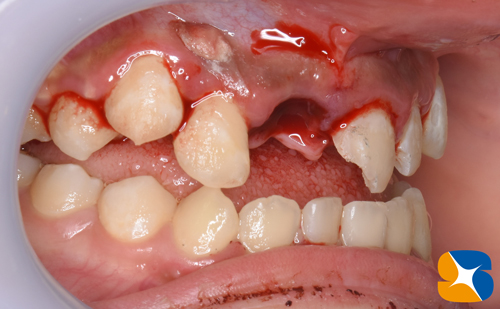

お子さんには頑張ってもらい、膿の袋を取り出す手術を行うことにしました。

CT画像と同等の場所と大きさの腫瘍が見つかりました。